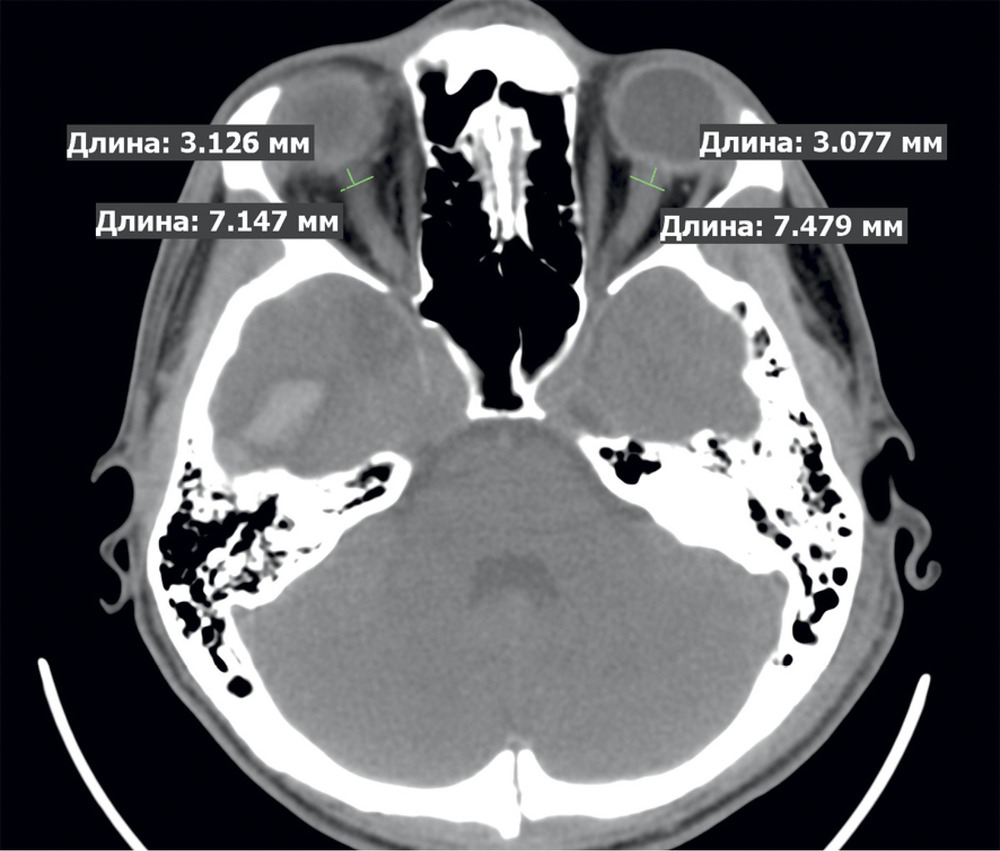

Оценка ДОЗН производилась «вслепую» двумя рентгенологами (Д.А.С. и Т.А.М.). Измерение ДOЗН проводилось с уровнем и шириной окна в диапазоне 25—300 едH. Величина ДОЗН оценивалась на расстоянии 3 мм от заднего контура глазного яблока (рис. 2).

Для дальнейшего статистического анализа выбирали большее из двух измерений ДОЗН. Анализировались только данные первого КТ-исследования с момента госпитализации. На рис. 3 представлена